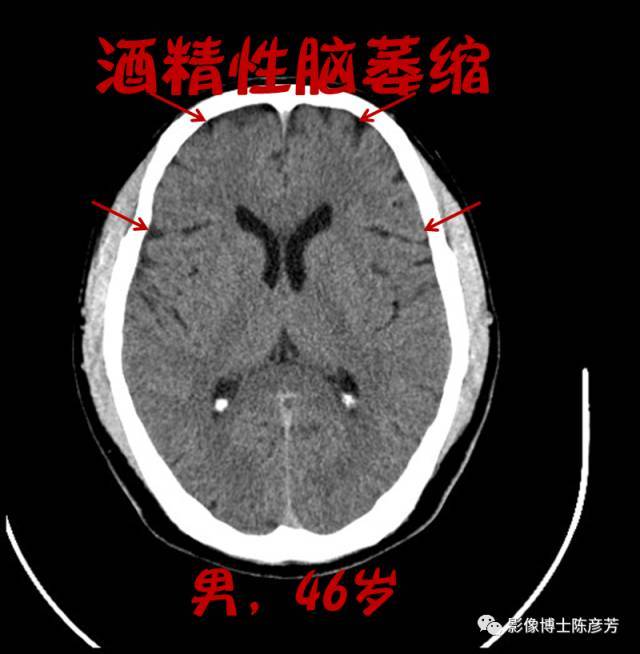

酒精性脑萎缩

酒精性脑萎缩,轻度脑萎缩

喝酒喝出脑萎缩,不是危言耸听!

脑萎缩ct

脑萎缩ct表现

脑萎缩ct图片

脑萎缩ct片子图片

脑萎缩ct图片解说